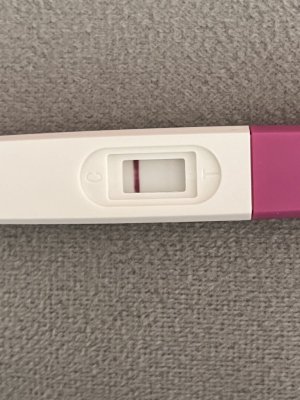

Kızlar merhaba bugün aşılamanın 11.günü yapıldığı günü saymazsam eğer , cuma günü kan vermiştim beta 0 çıkmıştı . Bugün bi test yapayım dedim testte böyle silik çizgi çıktı adetimi de tam kestiremiyorum pcos var bende 1-2 en fazla 3 gün kalmıştır. Testi ekliyorum böyle silik öğrenen varmı aranız da ?

Eklentiler

bence bebek var canım rabbim en hayırlısından nasip etsinKızlar merhaba bugün aşılamanın 11.günü yapıldığı günü saymazsam eğer , cuma günü kan vermiştim beta 0 çıkmıştı . Bugün bi test yapayım dedim testte böyle silik çizgi çıktı adetimi de tam kestiremiyorum pcos var bende 1-2 en fazla 3 gün kalmıştır. Testi ekliyorum böyle silik öğrenen varmı aranız da ?

Çok teşekkür ederim inşallahbence bebek var canım rabbim en hayırlısından nasip etsin